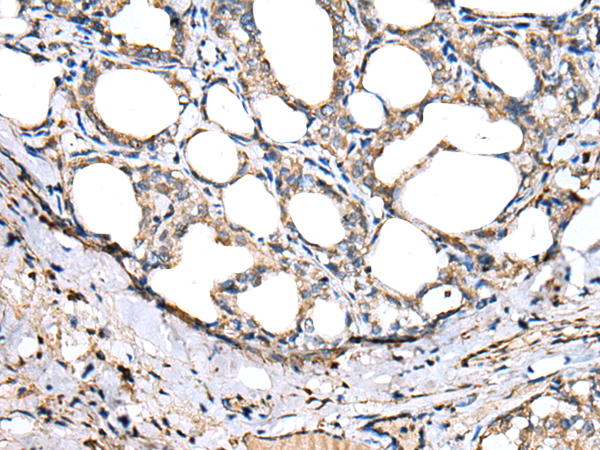

IHC positive control:

Human thyroid cancer

IHC Recommend dilution:

25-100